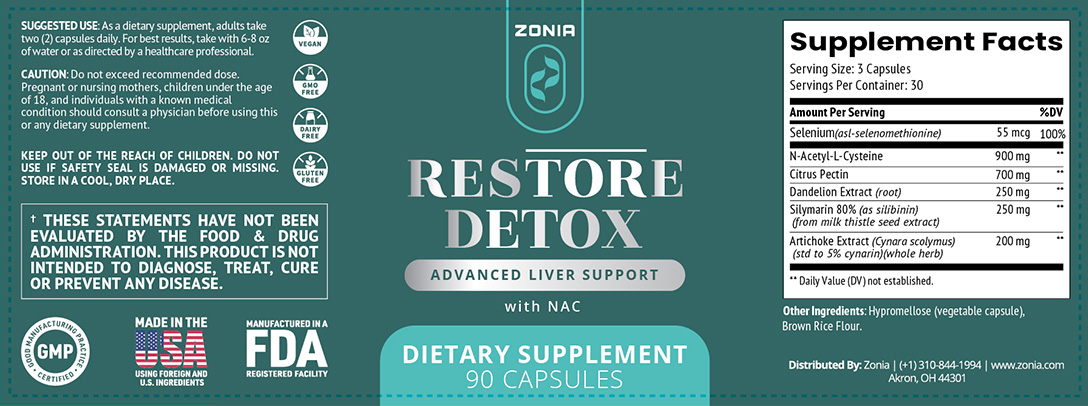

N-acetyl-L-cysteine (NAC), the effective detox agent that helps flush out heavy metals, pesticides, antibiotics and other environmental toxins from your body.

Citrus Pectin is a safe fruit-derived heavy-metal detox agent. It’s proven to support a side-effect-free, mild detox process, starting as early as in 24 hours.

And Selenium is our best bet because it has been shown to help rejuvenate our bodies and even help repair human DNA26.

An ancient detox powerhouse, Silymarin, has been used since 40 AD to cure snake bite poisoning.28

Dandelion Root is a powerful antioxidant and a natural tonic.

In various studies, artichoke leaf extract was shown to protect liver function and increase the production of bile, which helps remove harmful toxins from your liver.36

Restore Detox contains all these science-backed ingredients that help your body get rid of toxins so you can live a life free from low energy, memory problems, mood swings, insomnia and body aches

The ingredients found in Restore Detox promote a systemic body detox, significant toxin release, and deep support for your liver and kidneys, further aiding your natural detox process.

Restore Detox contains all-natural, science-backed detox agents that help your body flush out dangerous toxins…

While supporting your liver and kidneys in their natural detox process.

Citrus Pectin helps “bind” heavy metals and flush them from your system naturally in just 24 hours.

Selenium promotes the natural repair of your cells, organs and tissues, damaged by toxin overload.

Dandelion root, which helps your liver and kidneys filter out toxins more effectively and helps the body fight against cancer cells.

Milk Thistle (Silymarin), which assists the body in gently flushing out toxins coming from your foods and drinks.

Artichoke leaf extract, which helps protect liver function and increase the production of bile, which helps remove harmful toxins from your liver.

The best way to take the Restore Detox formula is 3 capsules daily with a glass of water or tea after your breakfast or lunch.